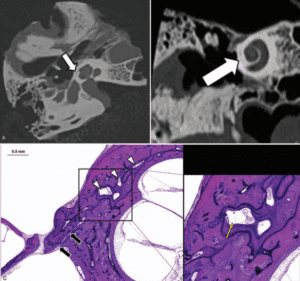

FIGURA 1: TC demonstrando FC, fina linha hipodensa que circunscreve a cóclea.

FIGURA 2: A e B: TC demonstrando FC em paciente adulto, tênue linha hipodensa que circunscreve a cóclea. C: imagens de estudo histopatológico revelando presença de medular óssea amarela na topografia da FC.

A FC (área curvilínea hipodensa ao redor da cóclea) correspondeu à histopatologia às áreas de medula óssea amarela, e em geral foram mais proeminentes no espécime fetal, onde havia menos ossificação.